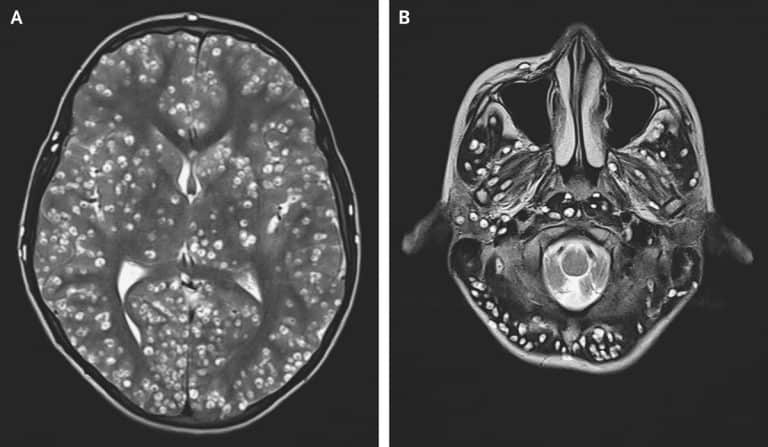

أفاد تقرير نُشر الأسبوع الماضي في دورية نيو إنغلاند جورنال أوف ميديسن، بوفاة شاب هندي في الثامنة عشر من عمره، بسبب انتشار الكثير من يرقات الديدان الشريطية في أجزاء مختلفة من دماغه. كان الشاب قد حضر إلى قسم الطوارئ وهو في حالة صرع شامل، ونظراً لتقدم الحالة، لم ينجح الأطباء في علاجه وتوفي بعدها بأسبوعين. تسمى تلك اليرقات بالكيسات المذنّبة (حيث تشبه اليرقة كيساً أو حويصلة ذات ذنَب أو ذيل)، وتسمى هذه الحالة بداء الكيسات المذنّبة العصبي.

يحدث عن طريق تناول أطعمة أو مياه ملوثة ببيض الديدان الشريطية (الذي يخرج مع براز الشخص المصاب بداء الشريطيات كما أسلفنا). ويعد تناول الخضروات الملوثة غير المطهية المصدر الأساسي للعدوى. وبنفس الآلية التي تحدث في العائل الوسيط، يخترق البيض جدار الأمعاء ويتطور إلى يرقات تنتشر في صورة كيسات في بعض أنسجة الجسم، كالجلد والعضلات والعينين، وكذلك الجهاز العصبي المركزي ليسبب داء الكيسات المذنّبة العصبي، وهو أخطر أشكال الإصابة.

وفقًا لبيان منظمة الصحة العالمية، “يمكن أن تكون لهذه العدوى آثار مدمرة على صحة الإنسان. وقد تتطور اليرقات (الكيسات المذنبة) في العضل والجلد والعين والجهاز العصبي المركزي. وعندما تتطور الكيسات في الدماغ، يُطلق على هذا المرض اسم داء الكيسات المذنبة العصبي. وتشمل الأعراض الصداع الشديد والعمى والاختلاجات والنوبات الصرعية، ويمكن لهذه الأعراض أن تصبح مميتة”.